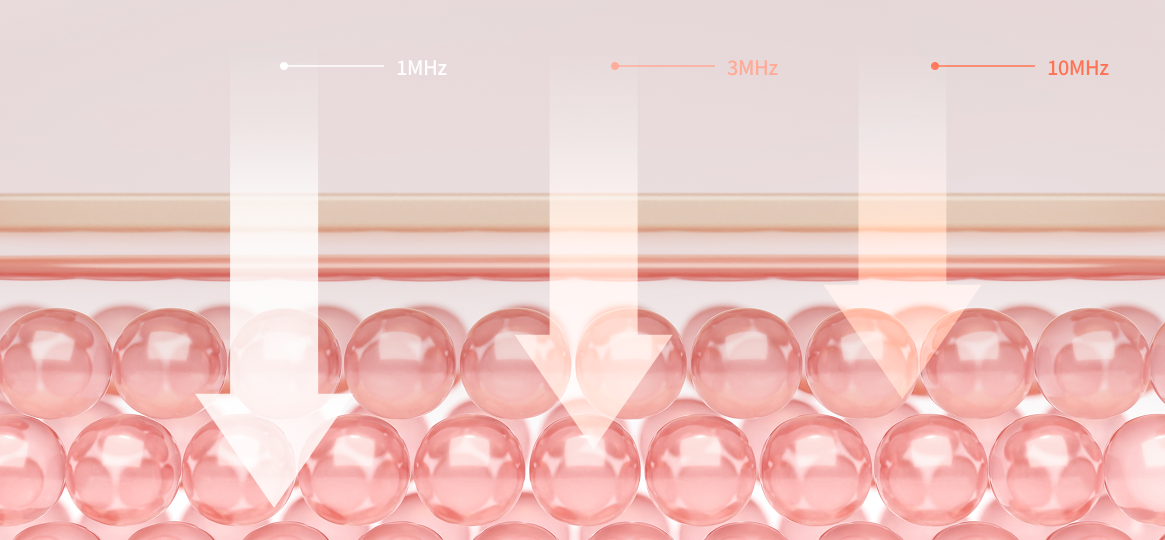

고밀도 초음파 관리로 1 MHz, 3 MHz, 10 MHz

등 서로 다른 주파수의 초음파를

빠르게 교차시키는

방식으로 피부에 미세한 진동과 에너지를 전달합니다.

LDM 시술 원리

세가지 초음파 파장의

흡합, 콜라겐효소의 증폭

1MHz/3MHz/10MHz의 초음파를 조사하는데

세 가지의 초음파 파장이 흡합되어 새로운

파장을 형성하고 피부 수분을 끌어당기면서

콜라겐 효소를 증폭시킵니다.

일반적인 리프팅 레이저와는 달리 피부 건조함을

유발하지 않으며, 손상된 피부나

노화된 피부의 재생을 촉진합니다.